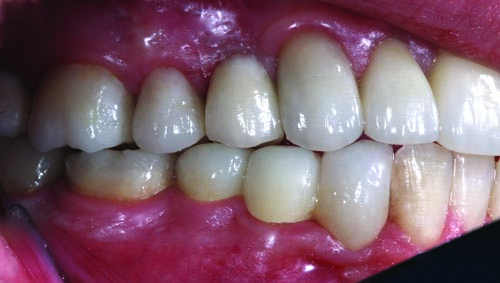

Fig. 3: The preoperative right lateral view shows evidence of the failing mesial/occlusal/distal (MOD) amalgam restorations in teeth #2, #4, #5, #29, #30, #31 and #32, as well as the need to replace missing tooth #3.